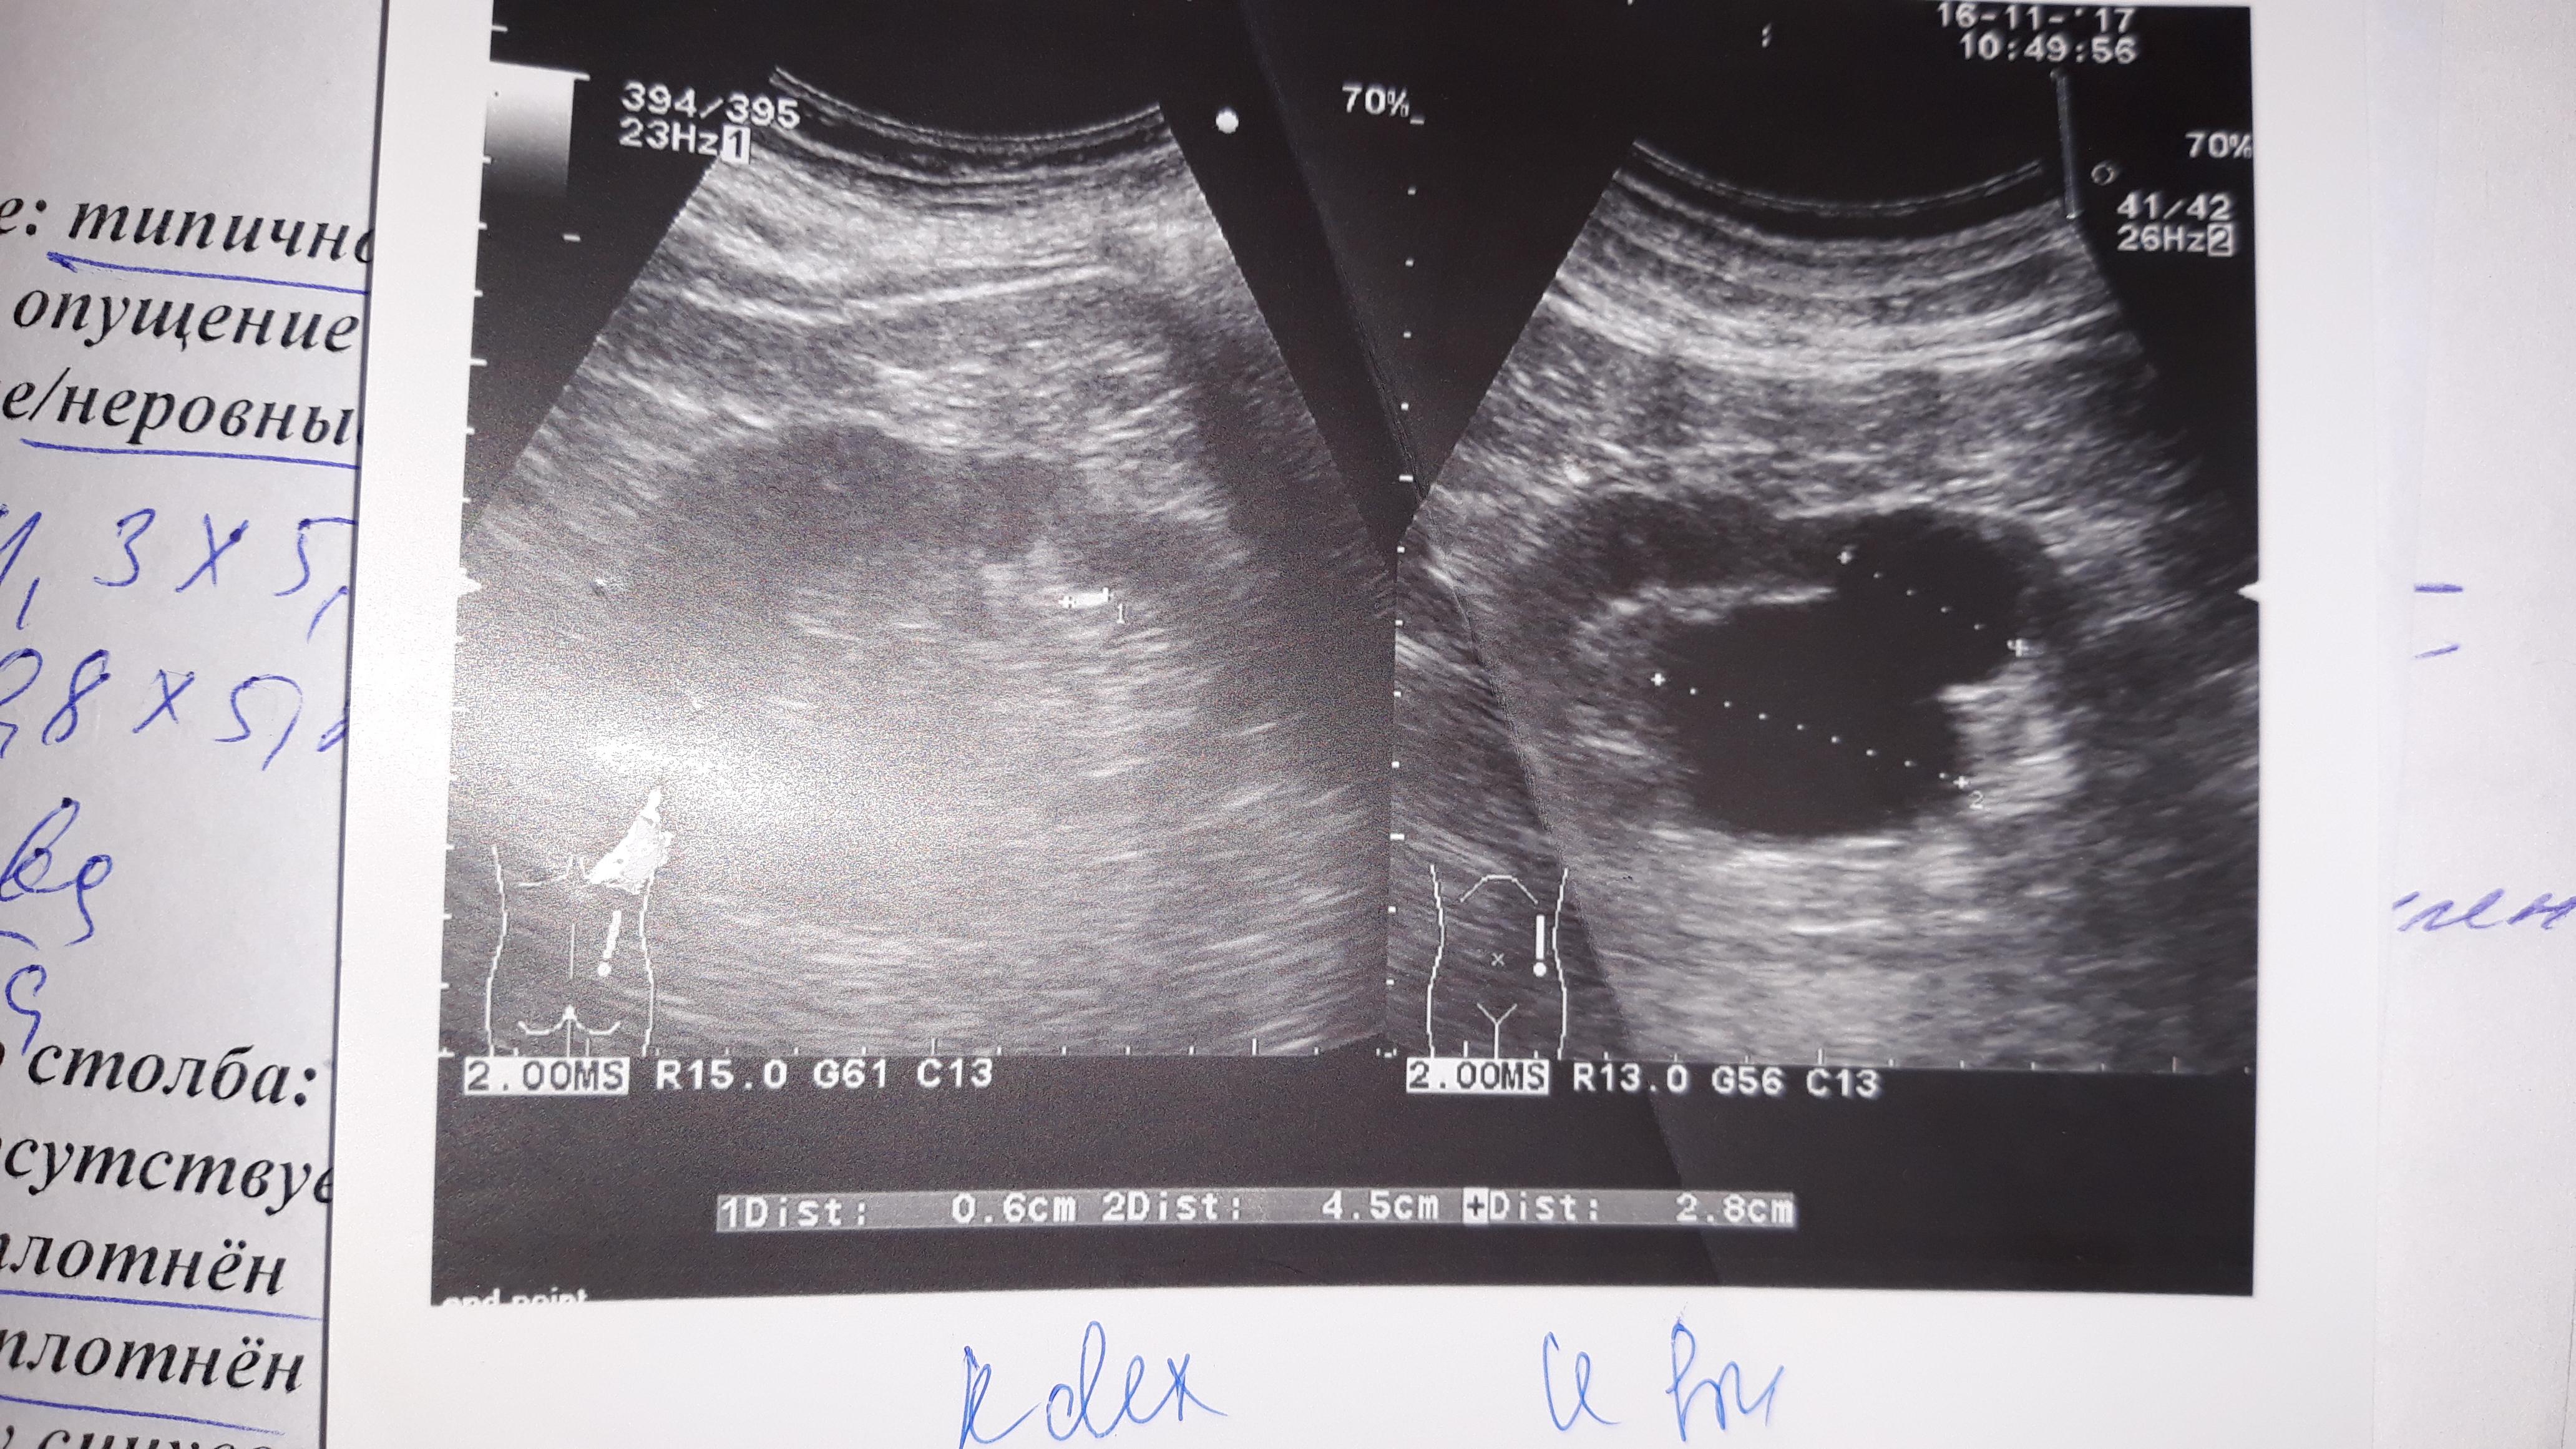

Диагноз: парапельвикальная киста левой почки, Размер 4,5 см в синусе и 2,8см в паренхиме. Впервые обнаружена в 2010 году с размерами 2,6смх2,2см и 1,9 х2,1см, находилась под наблюдением. После УЗИ 16.11.2017г рекомендована плановая операция. Вопрос : насколько оправдана операция?

По данным УЗИ киста довольно больших размеров и локализуется в чашечно-лоханочной области. Такая киста может нарушать функцию почки. Для диагностики надо сделать компьютерную томографию почек с контрастирование, чтобы оценить состояние чашечно-лоханочной системы - нет ли нарушения оттока мочи. И оценить результаты с урологом.